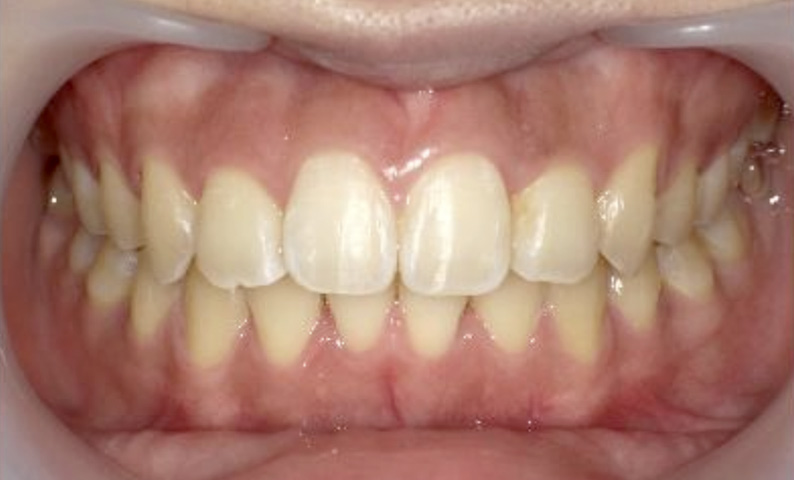

症例_025 上下顎の部分矯正

治療期間:13ヶ月金額:51万円+税女性前歯のガタガタ出っ歯

| Before | After |

|---|---|